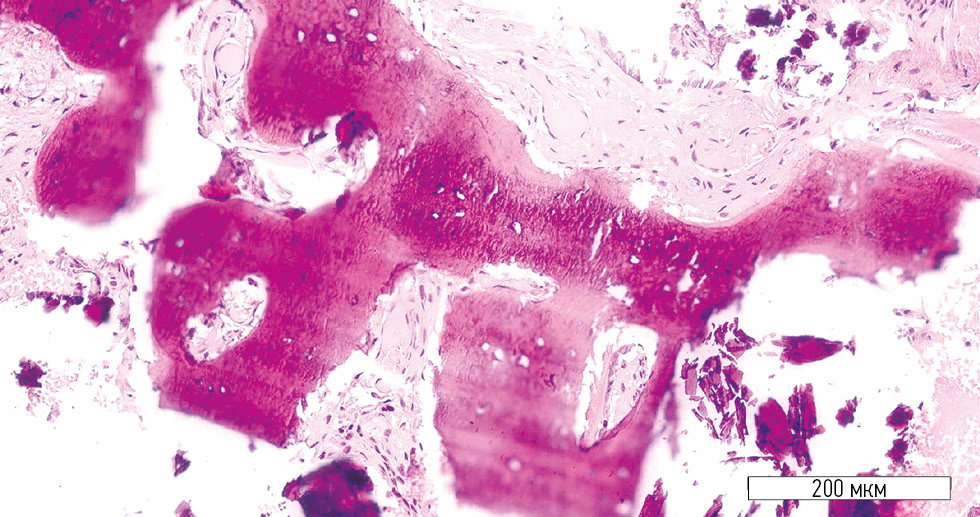

Closer examination of the bone lamellae revealed areas of non-uniform osteogenesis (Fig. 4). Maximum bone density was observed at the periphery of the trabeculae, whereas the central zones showed regions with immature osteons.

Fig. 4. Bone lamella with heterogeneous structure (treatment group). Hematoxylin-eosin stain; original magnification ×400.